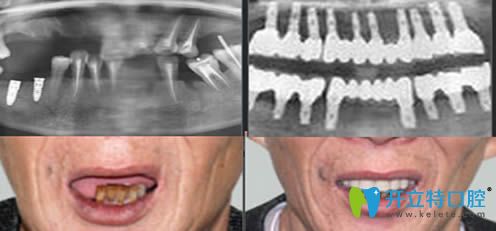

重慶皇仕口腔半口牙種植案例效果前后對比:

顧客:王先生

牙齒狀況:上牙及部分下牙缺失

治療方案:激光無痛即刻種植技術

完成時間:3小時

種植感言:3個小時就解決了多年的缺牙問題,顯年輕不說,關鍵是能和年輕時候一樣吃東西了,對效果非常滿意。